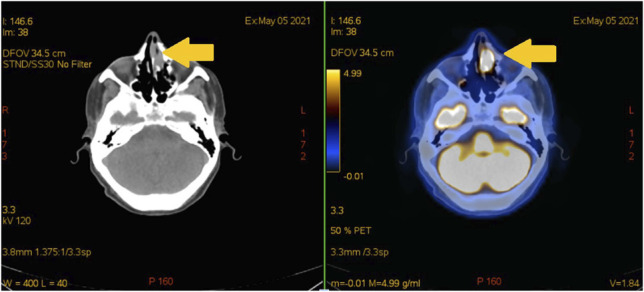

Rare extranodal NK/T-cell lymphoma: a diagnostic challenge and therapeutic approach.

Abstract Image